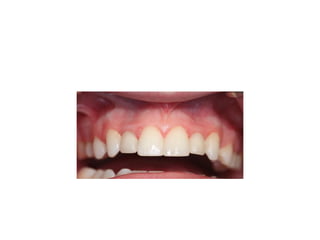

pre-op